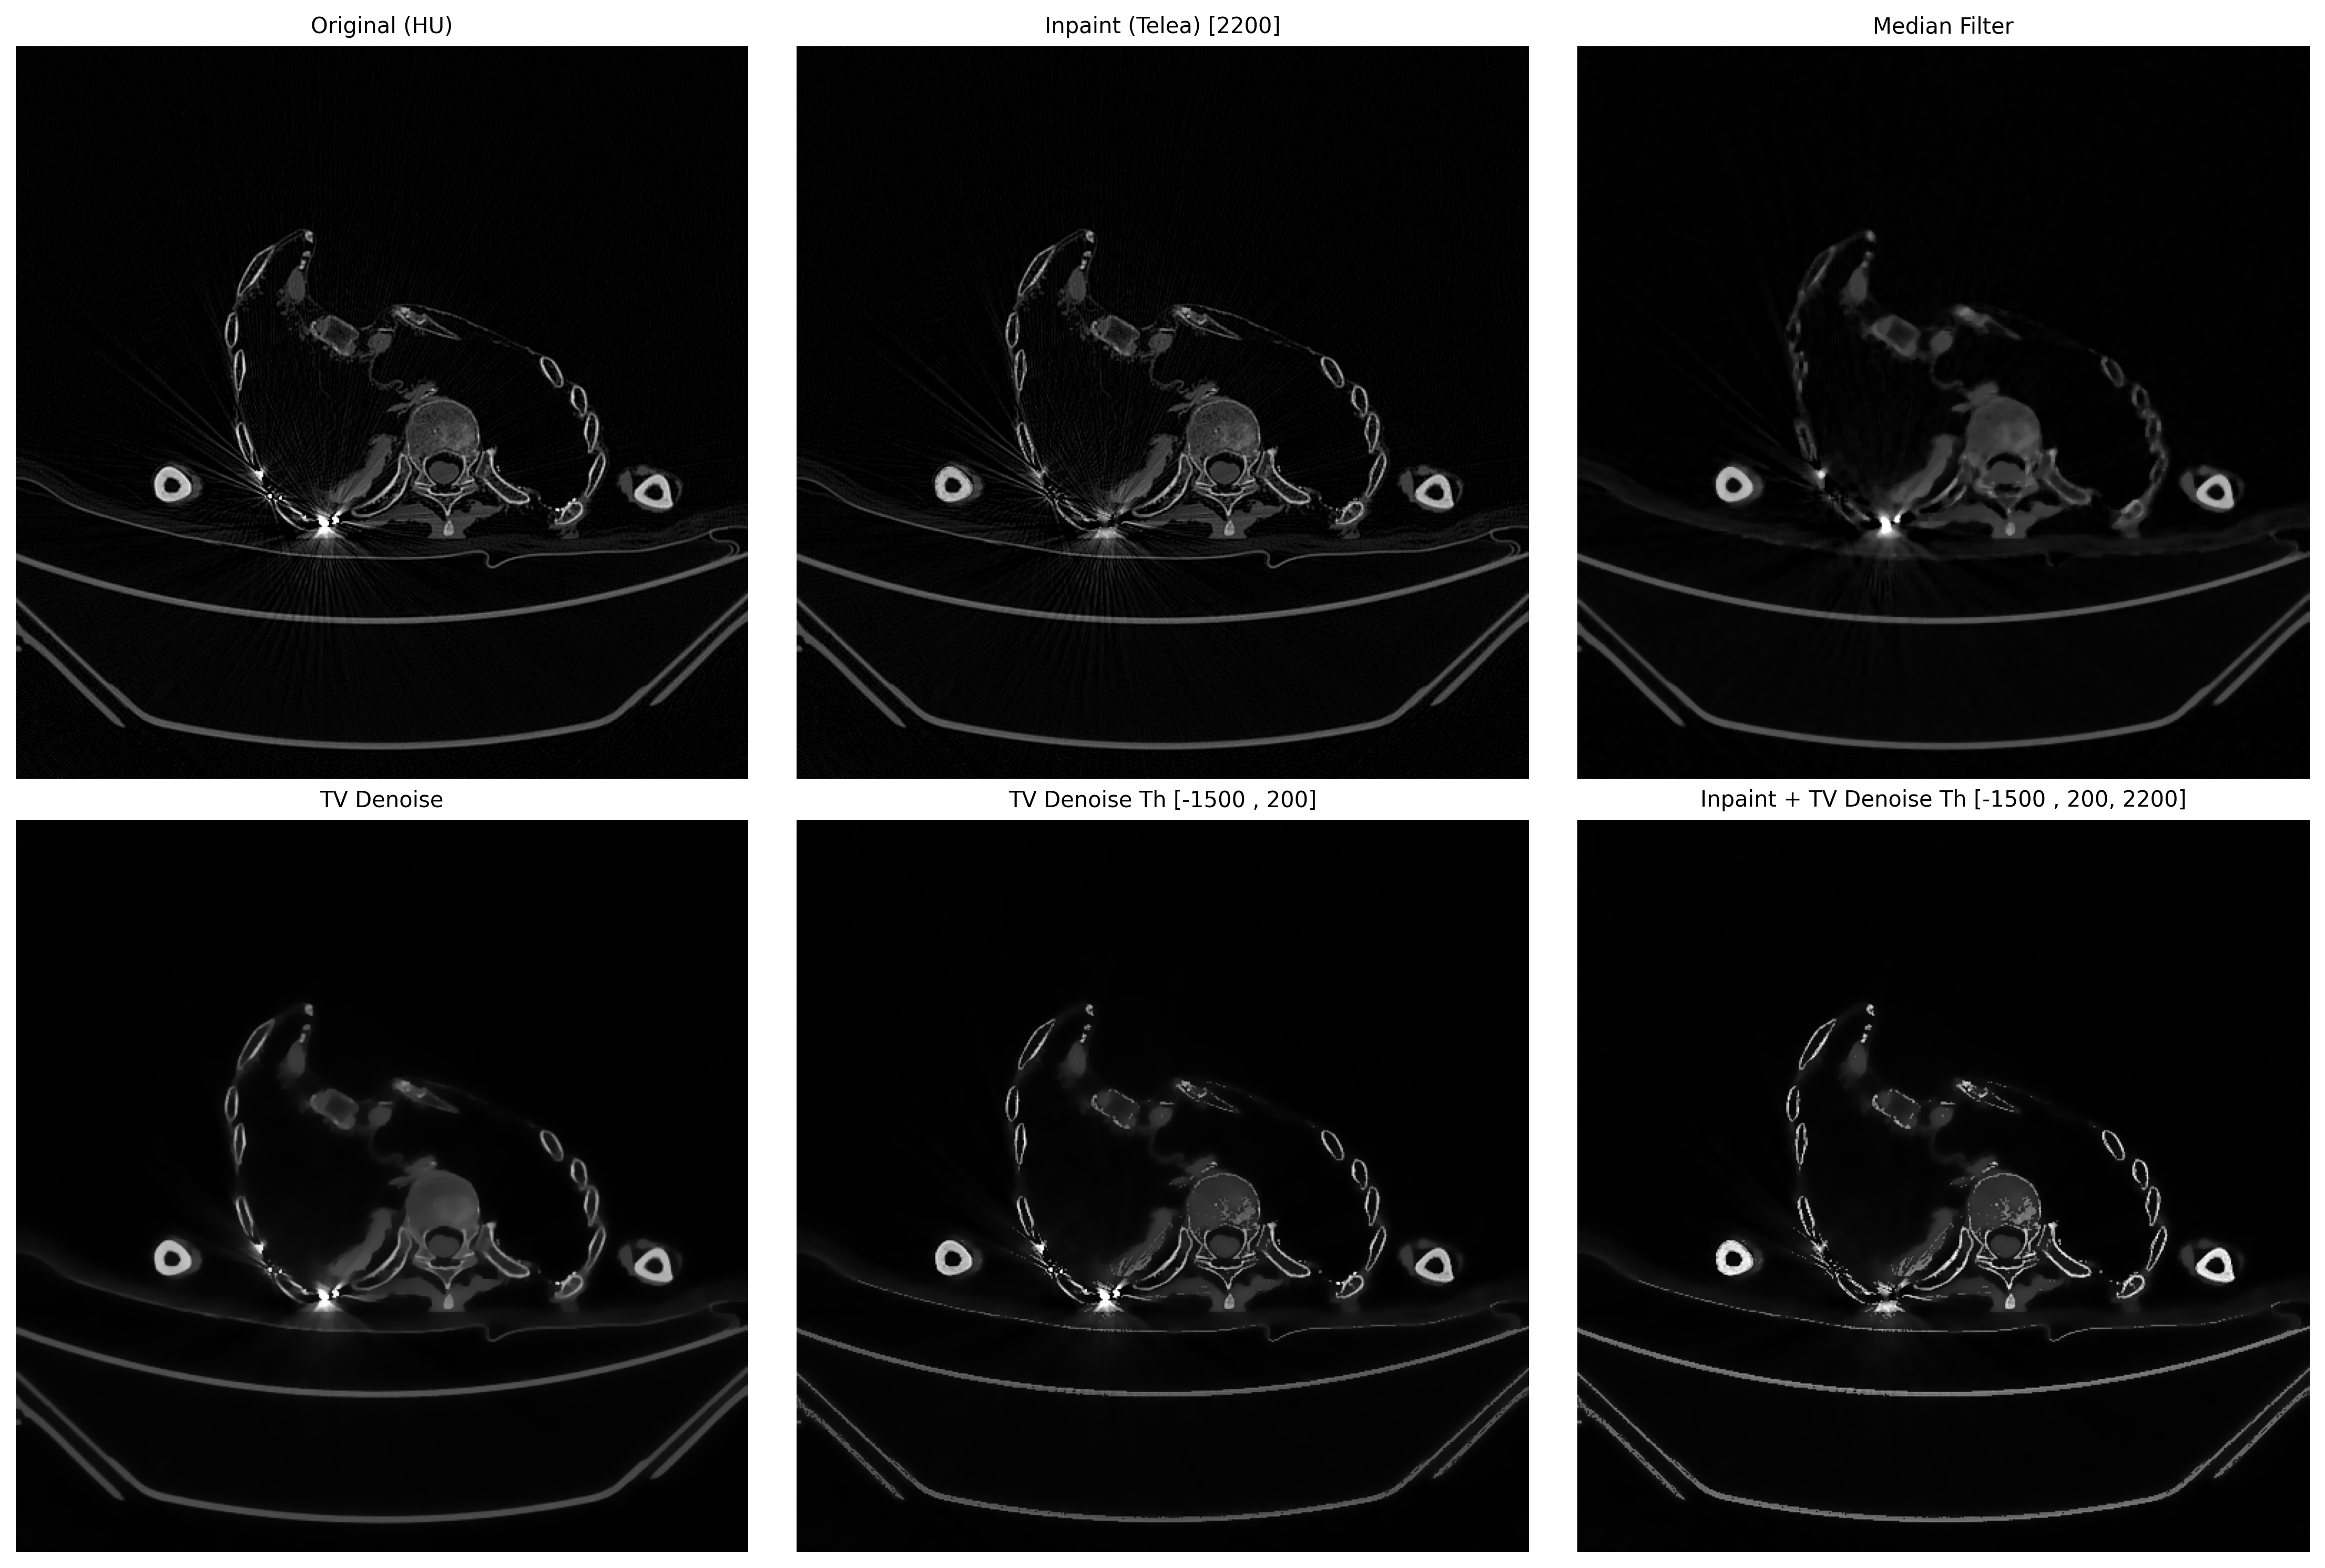

# 5. 汇总图

def create_summary(ct_hu, artifact, results, file_name):

fig, axes = plt.subplots(2, 3, figsize=(15, 10)) # 两行三列

axes = axes.ravel()

def show(i, img, title):

axes[i].imshow(img, cmap='gray', vmin=0, vmax=255)

axes[i].set_title(title, fontsize=10)

axes[i].axis('off')

# 0 号位:原图

show(0, exposure.rescale_intensity(ct_hu, out_range=(0, 255)),

"Original (HU)")

# 1 开始放 results

for idx, (name, img) in enumerate(results, start=1):

show(idx, img, name)

# 隐藏剩余空白子图

for j in range(len(results) + 1, 6):

axes[j].axis('off')

plt.tight_layout()

plt.savefig(f"metal_artifact_summary_{file_name}.png", dpi=300, bbox_inches='tight')

plt.show()

plt.close('all')

results = [

("Inpaint (Telea) [{}]".format(threshold), inpaint_opencv(ct_hu, mask)),

("Median Filter", median_filter(ct_hu)),

("TV Denoise", denoise_tv(ct_hu)),

("TV Denoise Th [{} , {}]".format(hu_min, hu_max), denoise_tv_th(ct_hu, hu_min=hu_min, hu_max=hu_max)),

("Inpaint + TV Denoise Th [{} , {}, {}]".format(hu_min, hu_max, threshold), inpaint_denoise_tv_th(ct_hu, hu_min=hu_min, hu_max=hu_max, threshold=threshold)),

]

create_summary(ct_hu, ct_hu, results, file_name)

Inpaint能去除金属,拖影使用TV Denoise。

其他案例,但需要更具直方图就行调整。